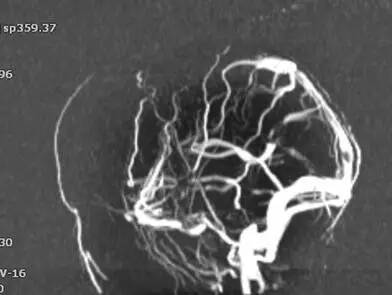

▼头颅MRV。

▼全颈脑血管造影术。